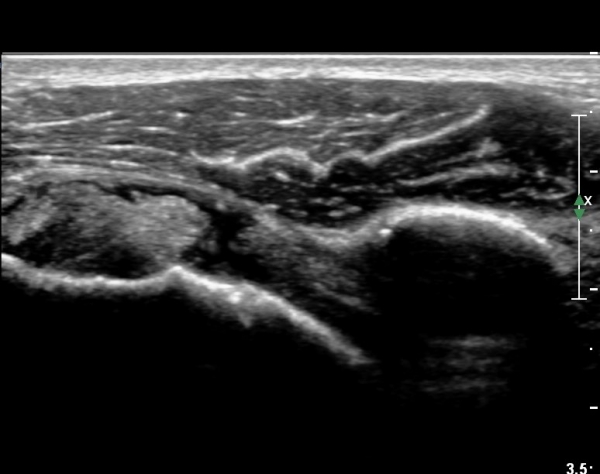

º¸¿© °ß°©ÇÏ±Ù°Ç ÆÄ¿­ÀÌ ÃßÁ¤µÈ´Ù(»çÁø 1). ŽÃËÀÚ¸¦ ¾à°£ ¾Æ·¡·Î À̵¿ÇÑ ÈÄ

ÆÈÀ» ¿ÜȸÀüÇϸ鼭 °üÂûÇÏ´Ï °ß°©ÇÏ±Ù°Ç ÆÄ¿­ÀÌ ¶Ñ·ÈÇÔ(»çÁø 2, 3).